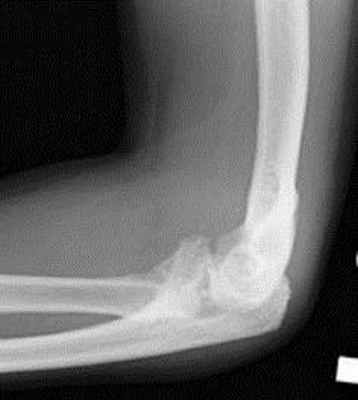

При переломе локтевого и венечного отростка без смещения накладывают гипсовую повязку сроком на 3-4 недели. При смещении фрагментов больше чем на 5мм при переломе локтевого отростка проводят оперативное вмешательство методом остеосинтеза (соединение костных отломков при помощи фиксирующих конструкций, которые обеспечивают неподвижность костных фрагментов). При вклинивании осколка в локтевой сустав при переломе венечного отростка оперативно удаляют этот фрагмент.

При несмещенном переломе головки и шейки лучевой кости на согнутый локтевой сустав накладывают лонгет с фиксацией лучезапястного и локтевого сустава и до середины плеча сроком на три недели. При смещении показан остеосинтез.

При переломах лучевой кости «в типичном месте» обычно проводится консервативное лечение. При наличии смещения отломков под местной анестезией выполняется закрытая репозиция с последующей иммобилизацией. Срок иммобилизации 4–6 недель с последующим назначением восстановительного лечения (физиотерапевтических процедур, лечебной гимнастики). В ряде случаев показано назначение препаратов кальция и сосудистых препаратов. Переломы костей проксимального отдела предплечья без смещения также обычно не требуют выполнения хирургического вмешательства. Для сохранения функции локтевого сустава важно раннее начало лечебной гимнастики.

Остеосинтез стержнями часто не обеспечивает стабильной фиксации, а введение прямого стержня в лучевую кость приводит к выравниванию физиологической кривизны лучевой кости, что ведет к нарушению ротационных движений.